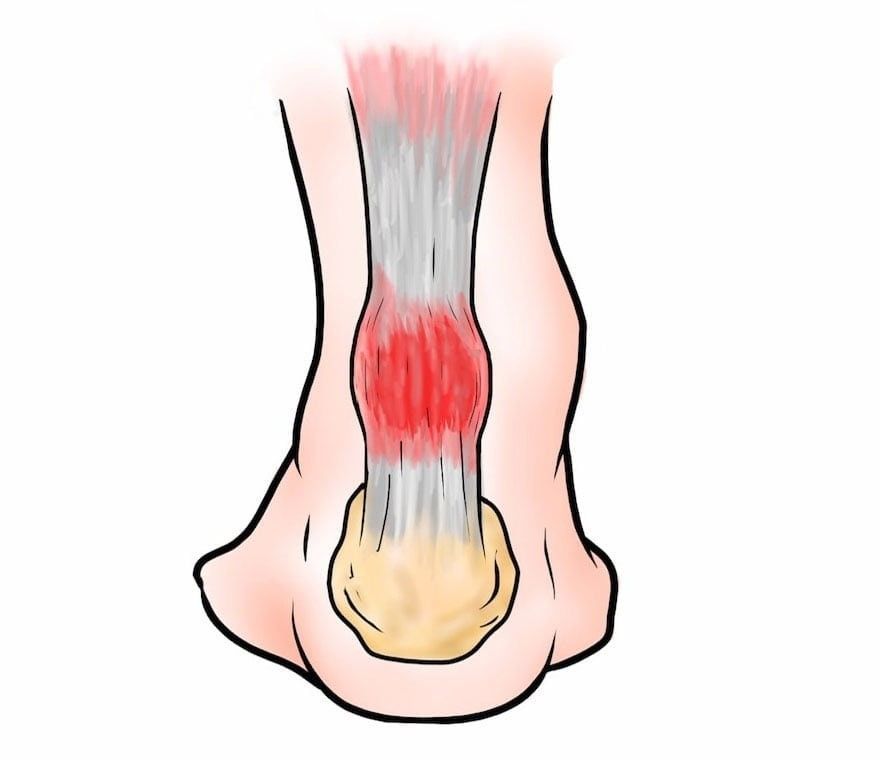

Тендинит Ахиллова сухожилия: симптомы и лечение

Раздел: Картинки на заметку